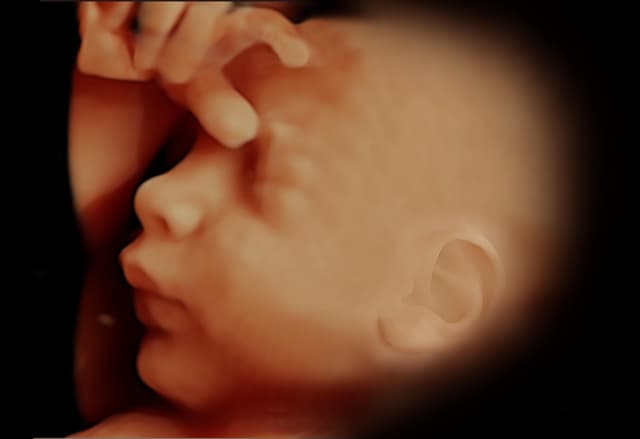

Tecnología avanzada que permite visualizar imágenes en tiempo real y en alta definición del feto, mostrando movimientos y rasgos faciales con gran detalle.

Ecografía 4D HD Live